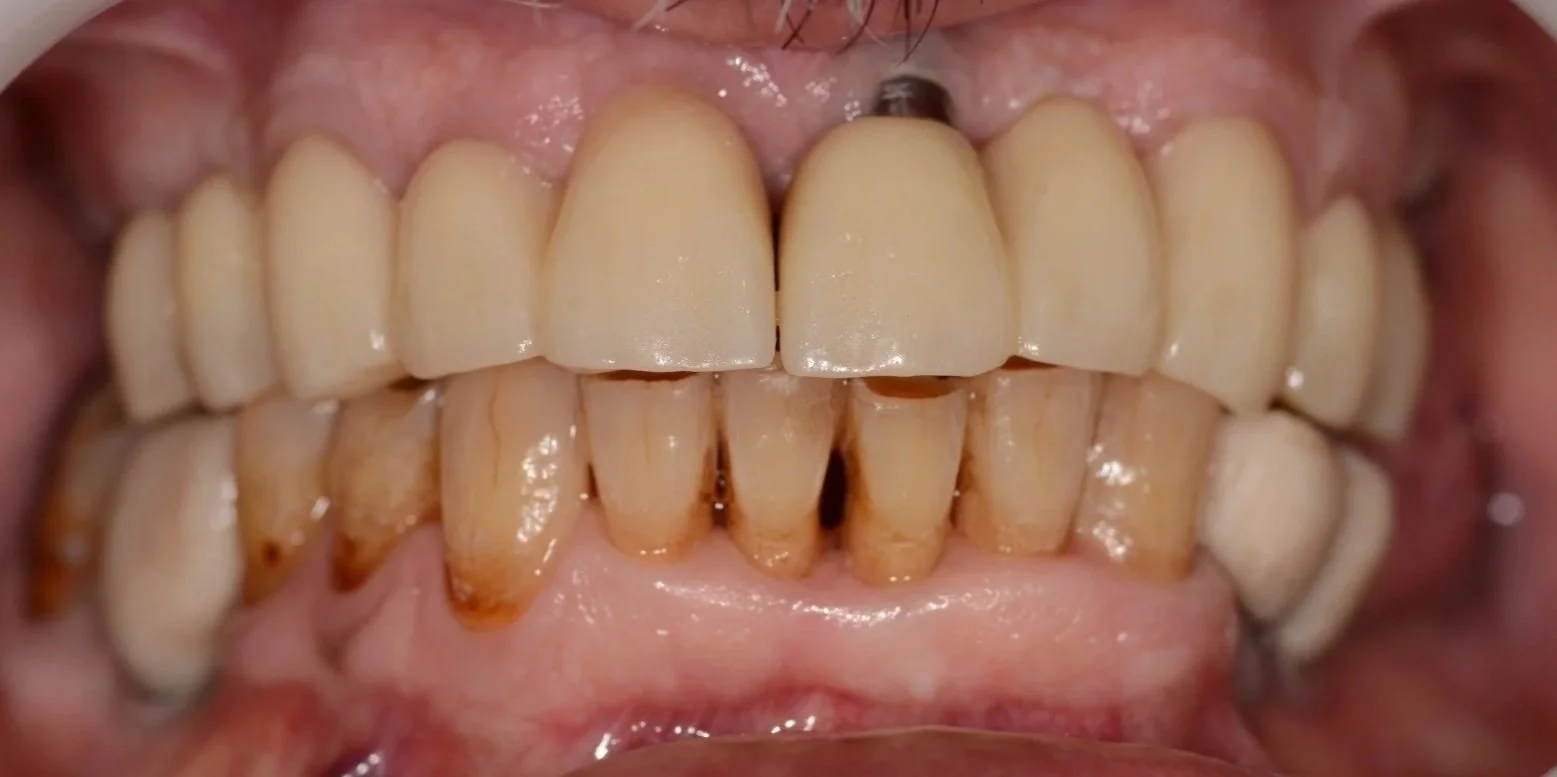

Antes

DIAGNÓSTICO: Presenta riesgo y actividad de caries, periodontitis estadío II grado A generalizada, brechas desdentadas clase III del sector I y II (de 15-17 y de 25-27) y sector III (de 35 a 37).